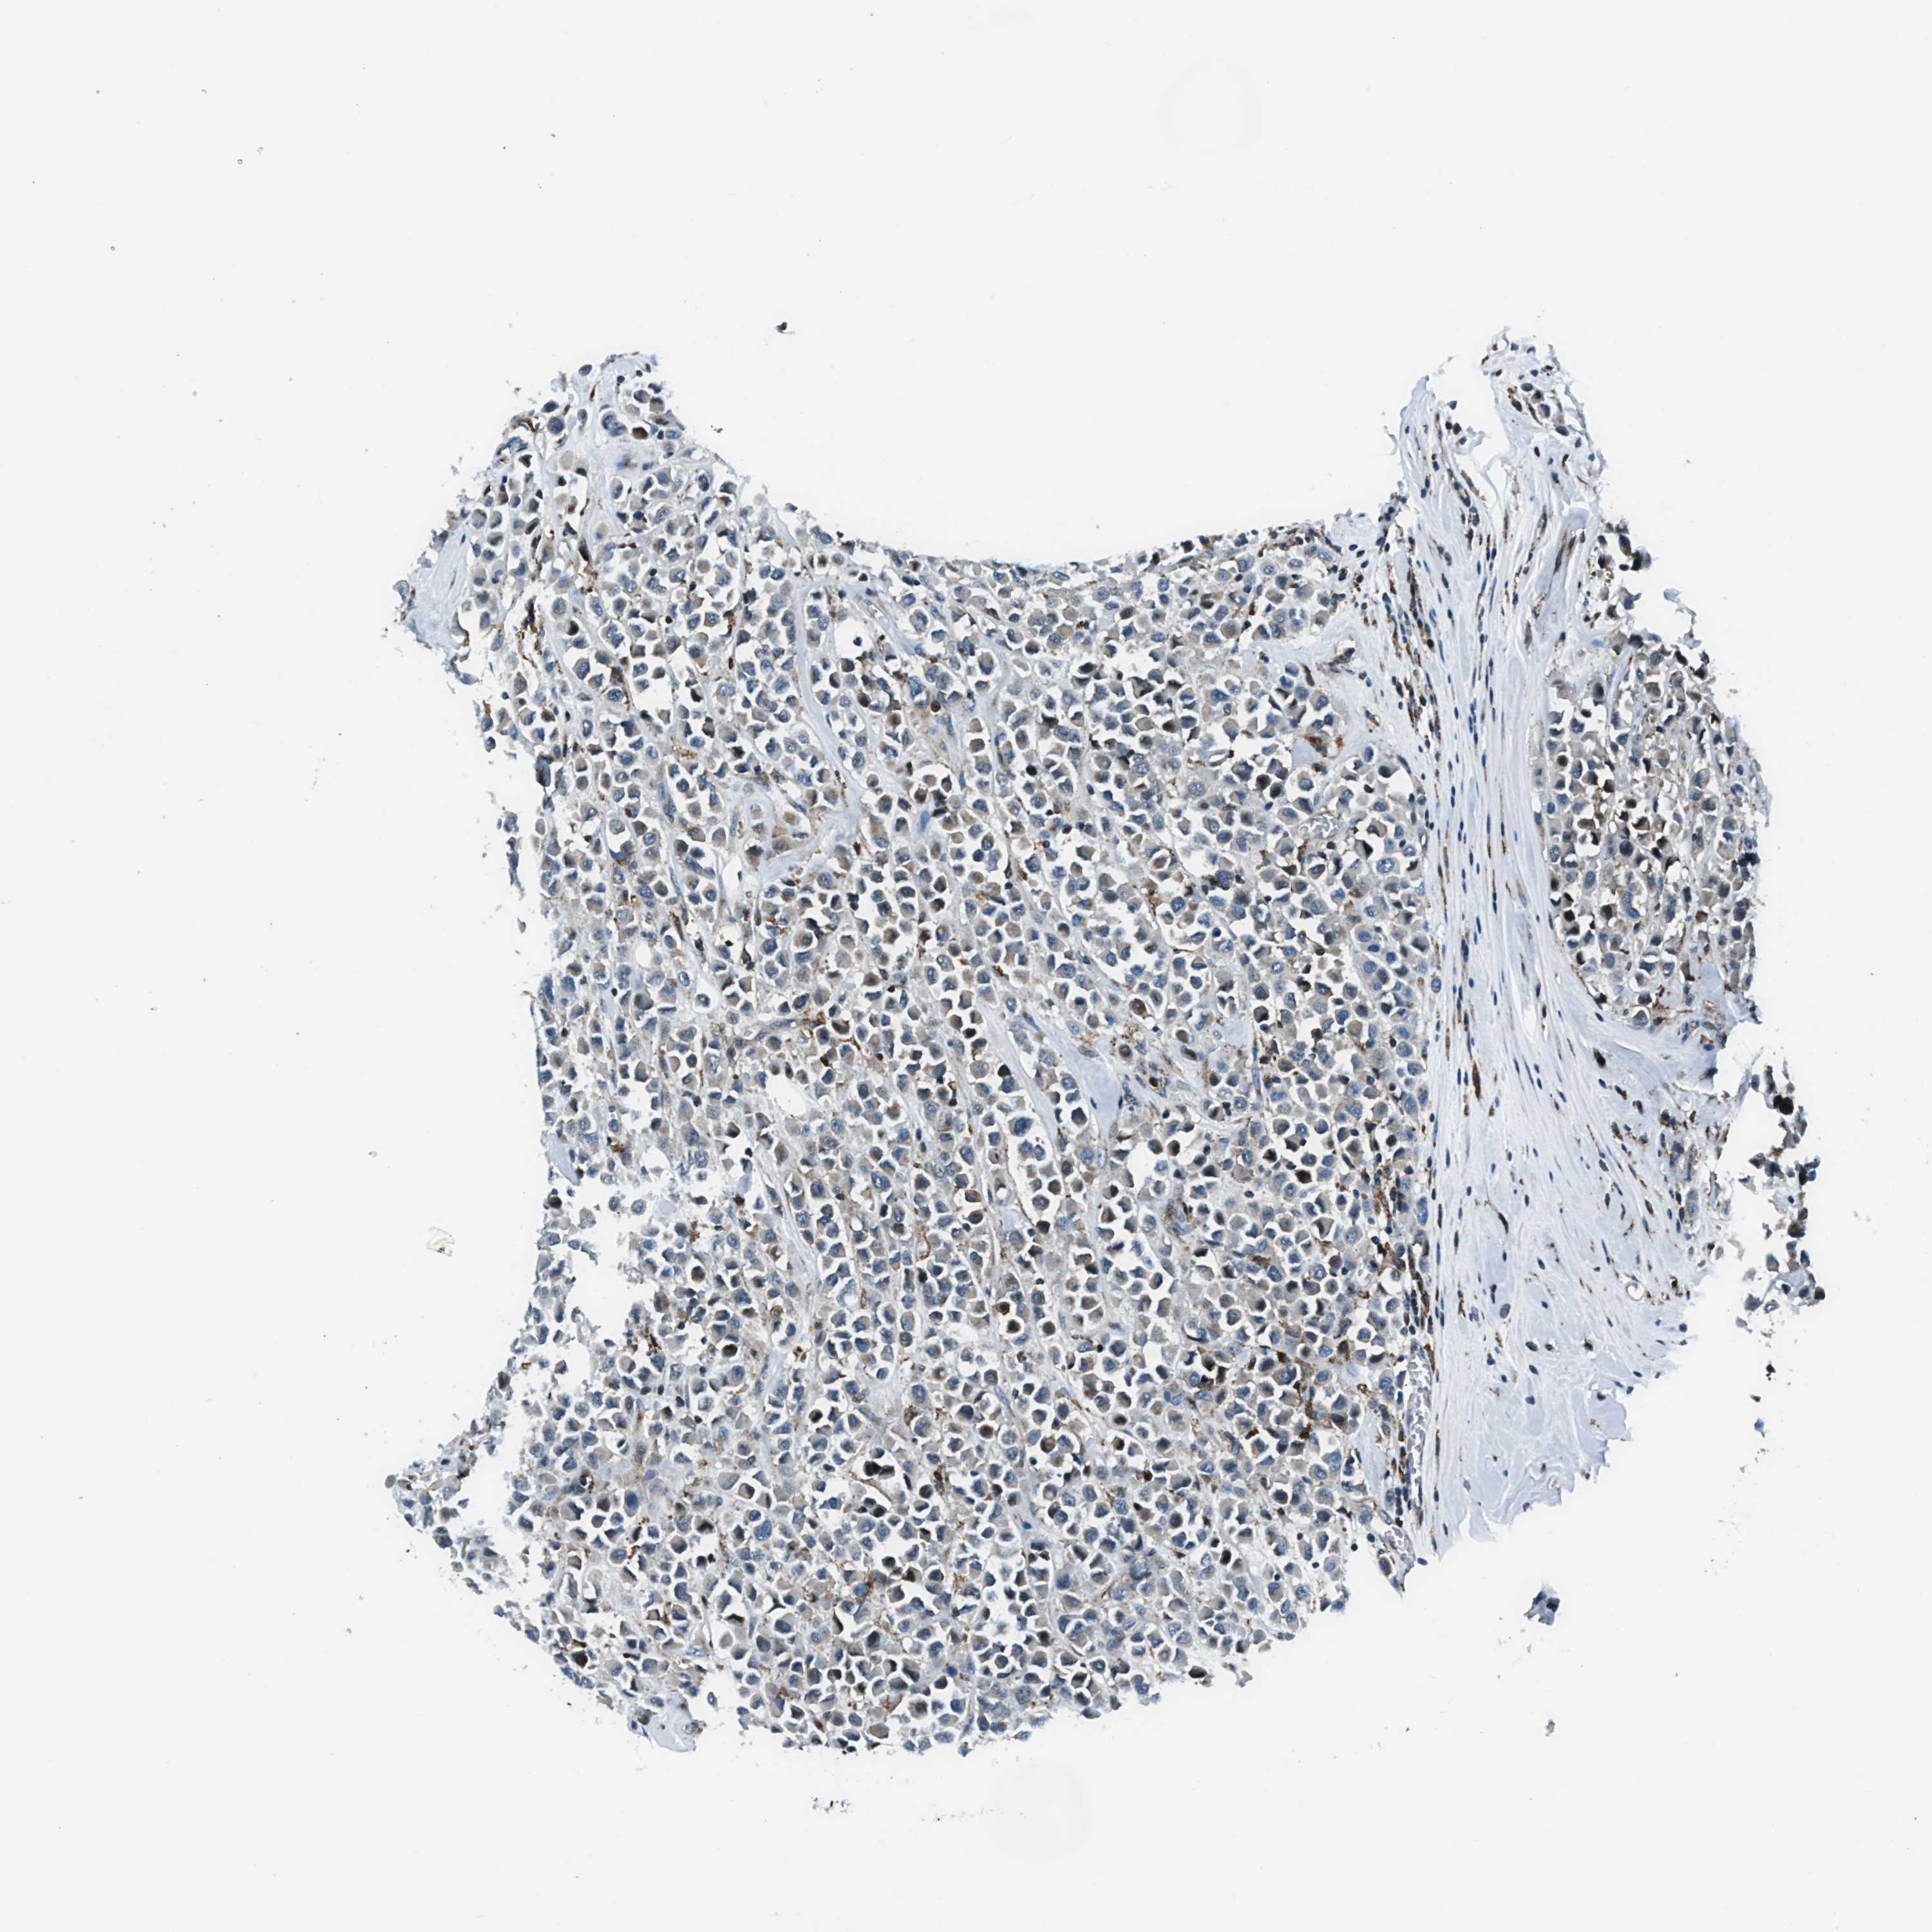

BRCA TCGA BRCA VALIDATION PROTEIN EXPRESSION